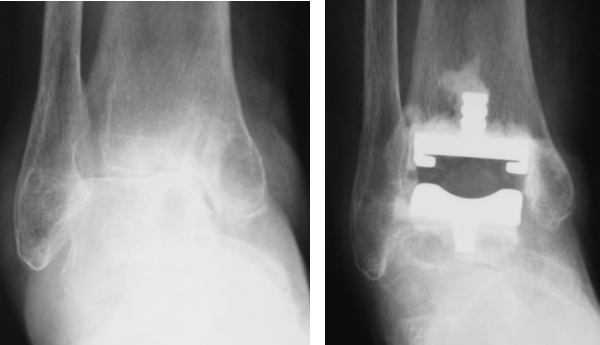

OA、RAの足関節障害には人工足関節置換術(total ankle arthroplasty: TAA)(図9)や関節固定術を行います。TAAは距踵病変がなく、比較的変形の少ない例に施行され、可動性を保つことができます。固定術は高度変形にも適応があり、関節の安定化が期待できます(図10)。RAは距踵関節にも破壊が生じやすいため、距腿関節と距踵関節(Tibio-talo-calcaneal: TTC)を同時に逆行性髄内釘で固定することもあります(図11)。

図9:人工足関節置換術